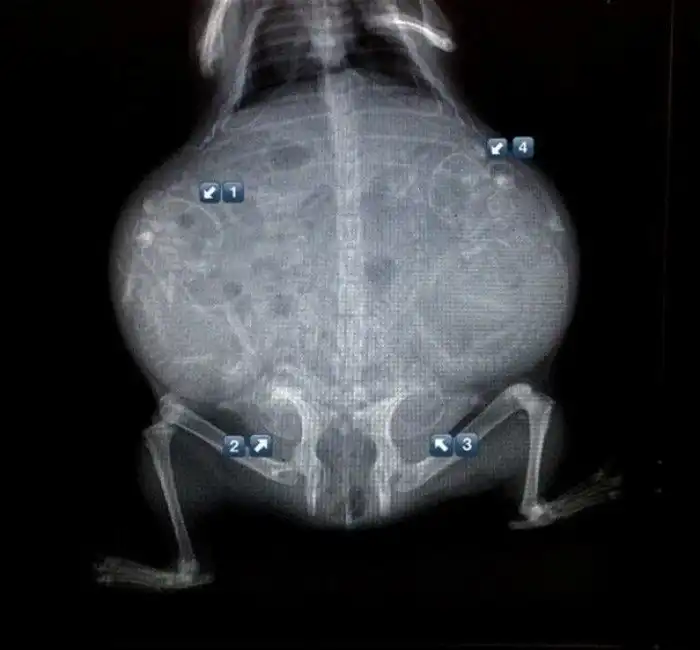

Специалисты, которые по долгу своей работы наблюдают животных, готовых принести потомство, поделились этими удивительными рентгеновскими и ультразвуковыми снимками.

2. Беременная черепаха